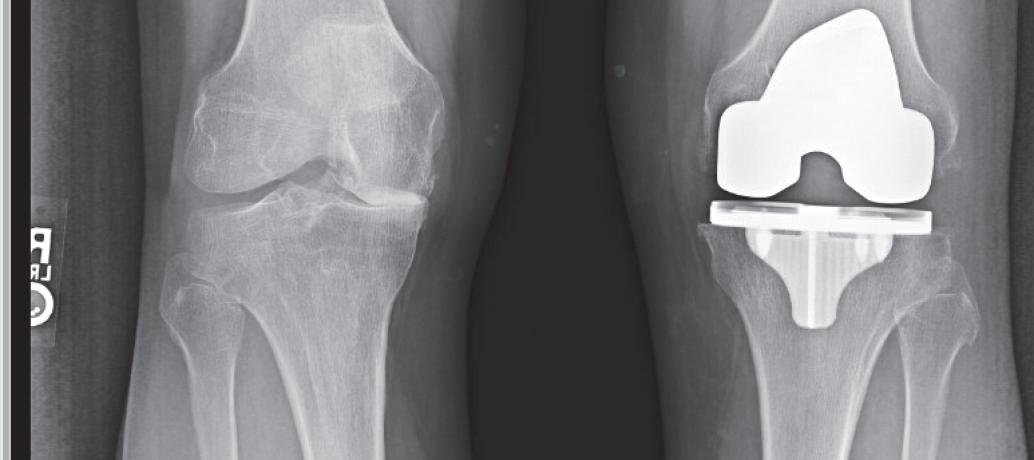

EPHsurgeon attacks knee pain on allfronts

Knee pain is an extremely common medicalproblem that canbecausedbyinjury, wear andtearorarthritis. Thereare many approaches physicians cantaketofix knee issues,fromminor treatmentstomajor surgery.

“The knee joint, even though it is ahinge joint, is a fairly complexjoint that has alot of different anatomical partstoitthatcan be fairly complicated,”saidEstes Park Health orthopedic surgeon Dr.Gavin Bishop.“Thecause of pain with akneecan be multiple sources. Oftenpeoplethink that it is just arthritis, butthere’s also apossibilitythatitcould be amultitude of things.”

Some of themorecommon causes of knee pain include patellafemoral syndrome wherethe kneecap is involved in asignificant amount of forceonthe frontofthe knee.

“Whenwe’re standing,it’s abouttwo timesour body weight,” Dr.Bishop said. “Whenwe’re goingupand down stairs or hiking up a mountain,it’sabout eightor nine timesour body weight.”

Patients canalsoexperience ligament or meniscus problems.These createstabilityand cushionfor theknee.

When people come to see Dr.Bishopthe first time,he must assess what is goingon.

“The first thingwedois get astory,soweknowhow or wherethe pain or discomfort is coming from,” Dr.Bishop said.“We also getx-raysto evaluate thebonystructures of thekneeand then agood physical exam.”

Dependingonthe diagnosis, specialistshavemanyinterventionstotry andease thepainordiscomfort.

“Physicaltherapy canbe exceedinglyhelpful as far as strength around theknee andbalance in theknee,”Dr. Bishop said.“Thereare certain kindsofinjections. Cortisone

“Wedon’t have away to bringthe cartilageback,”Dr. Bishop emphasized.“Theonlysurgicalfixfor that is atotal knee replacement. We cantry more conservative approaches untilit isn’tworking anymore. Then it’s ultimately up to thepatient to decideifthe next step is jointreplacement.”

is oneweuse afairamount, whichisastronganti-inflammatory whichhelps dull,achingpainwithinthe knee.Anothertypeofinjection which is only approved by theFDA forthe knee but is currently used forsomecosmetics is hyaluronic acid.That, too, can help with some of the inflammation in theknee. Some peopleliketothink of it as somethingthatcan help smooth out theknee. Anotherapproachis amultitude of braces,everythingfromaneoprenesleeve to abrace that has struts and supports that canbehelpful forthe specificneeds of that knee.”

Dr.Bishopalsoadvises certain patients to useheat, ice, non-steroidalanti-inflammatories,orTylenol

Alot of theseinterventions canmakekneeproblemslike irritation or limitedrange of motion more manageable,especially in thecaseofosteoarthritisordegenerativejoint diseasewhere thecartilage is just worn down.

“However,wedon’t have away to bringthe cartilage back,” Dr.Bishopsaid. “The only surgical fix forthatisa total knee replacement. We cantry allthose approaches untilit isn’tworking anymore.Thenit’s ultimately up to thepatient to decide if thenextstepisjoint replacement.”

is essentiallyaprocedure in

whichthe surgeonremoves theold part of thekneeand insertsanew device,replacingthe jointsurfaceswith metaland plastic.

During thesurgery,Dr. Bishop makesanincision rightupthe frontofthe knee,right over thepatella. Underneaththe next surface, he makesacurvedincision around thepatella to move thepatella outofthe way. Then he exposesthe femur, thetibia,and thepatella.He uses specialdevices to make accurate cuts of thosebones Then he places metalon thosebonesand then plastic in betweenatcertain stress points so that theligaments canfunctionthe waytheyare supposed to function.

“The ultimate idea is to recreatethe alignmentand the function of thekneeasitwas originally designed by takingoffaslittleboneaspossible andputting on an implant that will recreatethatjoint,”

Dr.Bishop said

Patients getupand move on thesameday as theirprocedure.Mobilityisimportant shortlyafter surgerytomaintain that rangeofmotion, so scar tissue does notdevelop. At twoweeks,mostpeopleare walking(some with an assistive device). By sixweeks, most people arewalking withoutthe assistivedevice.

“It’sthe outcomes that are most valuable to me,”Dr. Bishop said.“Ilikeitwhenpa-

tients do well andget back to theactivitiestheyenjoy doing like hiking andtakingpartin sports.”

Oneofthe many advantagesofhavingyourtotal knee replacementsurgery at EstesParkHealthisbeing closetohome. If youlivein this area andyourfamilyand friendsare here to support you, that canbeextremely valuable in your recovery.

“I have yearsofexperience doingjoint replacements in Longmont,” Dr.Bishop said. “I have alarge groupofpatients whohavebeenvery happywiththeir procedure. I’mexcited to bringthatsame technology,thatsameability, here to EstesPark. Come see me.Itstartswithaconversation.I’d be happytosee you. We woulddiscuss what the mainissuesare,what’sbotheringyou,whatthingswecan offer youtoimprove your activity andwhatyou want to do in your life.”

Totalkneereplacement